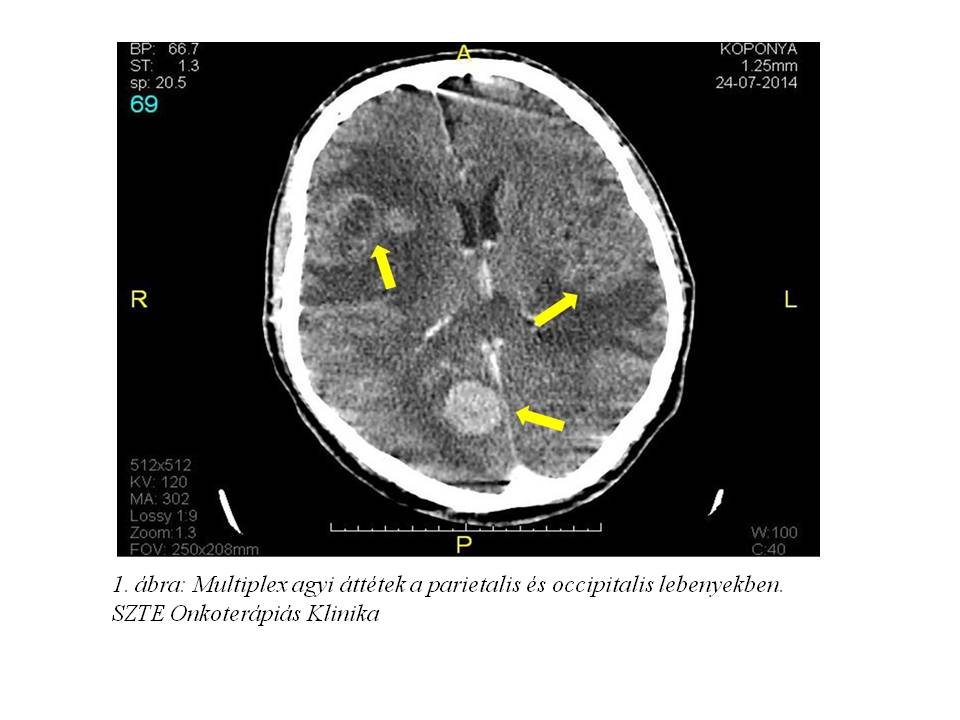

Egy 56 éves férfi betegünk kórtörténetét mutatom be, akit az SBO-ról vettünk át osztályunkra fejfájást, szédülést, hányingert és hányás okozó ismeretlen primer tumor multiplex agyi áttéteinek palliatív irradiaciójára (1. ábra, 2 ábra).

A kezelés megkezdése előtt kontroll koponya CT vizsgálat készült, mely a korábbi multiplex gócoknál regressziót véleményezett (7. ábra, 8. ábra).